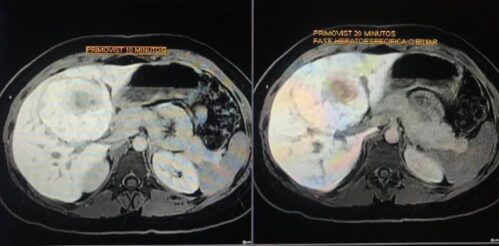

12.- En la evaluación con medio de contraste, se evalúa la relación arterial y de las venas, esto puede servir para buscar la arteria central relacionada con la hiperplasia nodular focal o bien, para evaluar la relación con las estructuras vasculares que son muy importantes para el planeamiento quirúrgico .

en este caso, aún cuando los hallazgos son atípicos tanto para hiperplasia nodular focal como para adenoma, nos inclinamos hacia el diagnóstico de adenoma debido a los antecedentes de la paciente, el tamaño de la lesión, el área de sangrado, el contenido de grasa.